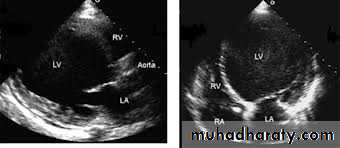

$Echo:

important in diagnosis :

1- LV hypertrophy 2- small LV cavity 3- SAM 4-ASH 5-impaired diastolic relaxation

6- mitral regurgitation 7- subaortic gradient if obstructed